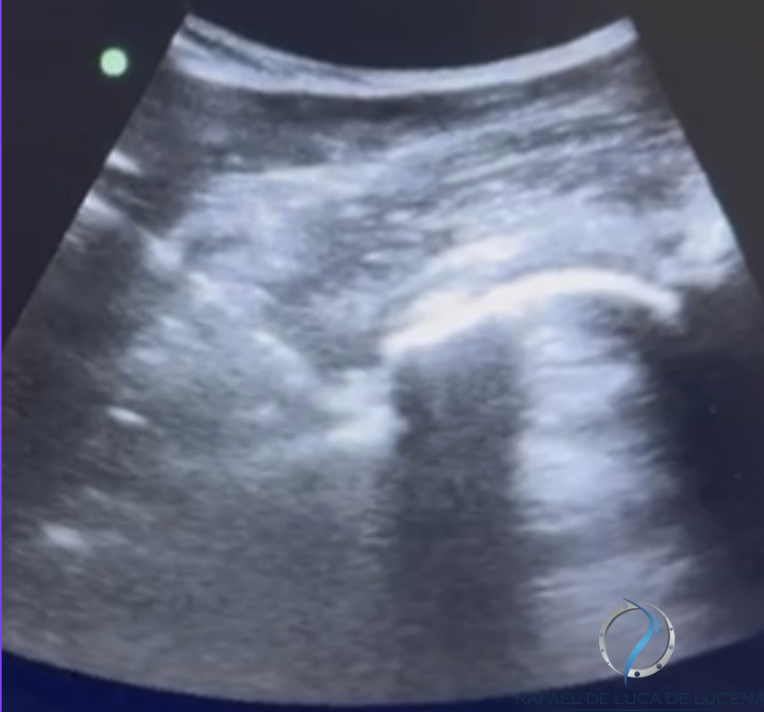

É a aplicação de fármacos ou substâncias terapêuticas diretamente na articulação do quadril (intra-articular) ou em estruturas periarticulares (bursas/tendões). Realizamos com ultrassom ou fluoroscopia para aumentar a precisão da agulha, reduzir riscos e melhorar o conforto do paciente.

- Guiada por imagem ( ultrassom ou radioscopia ): maior acurácia que técnicas por marcos anatômicos.